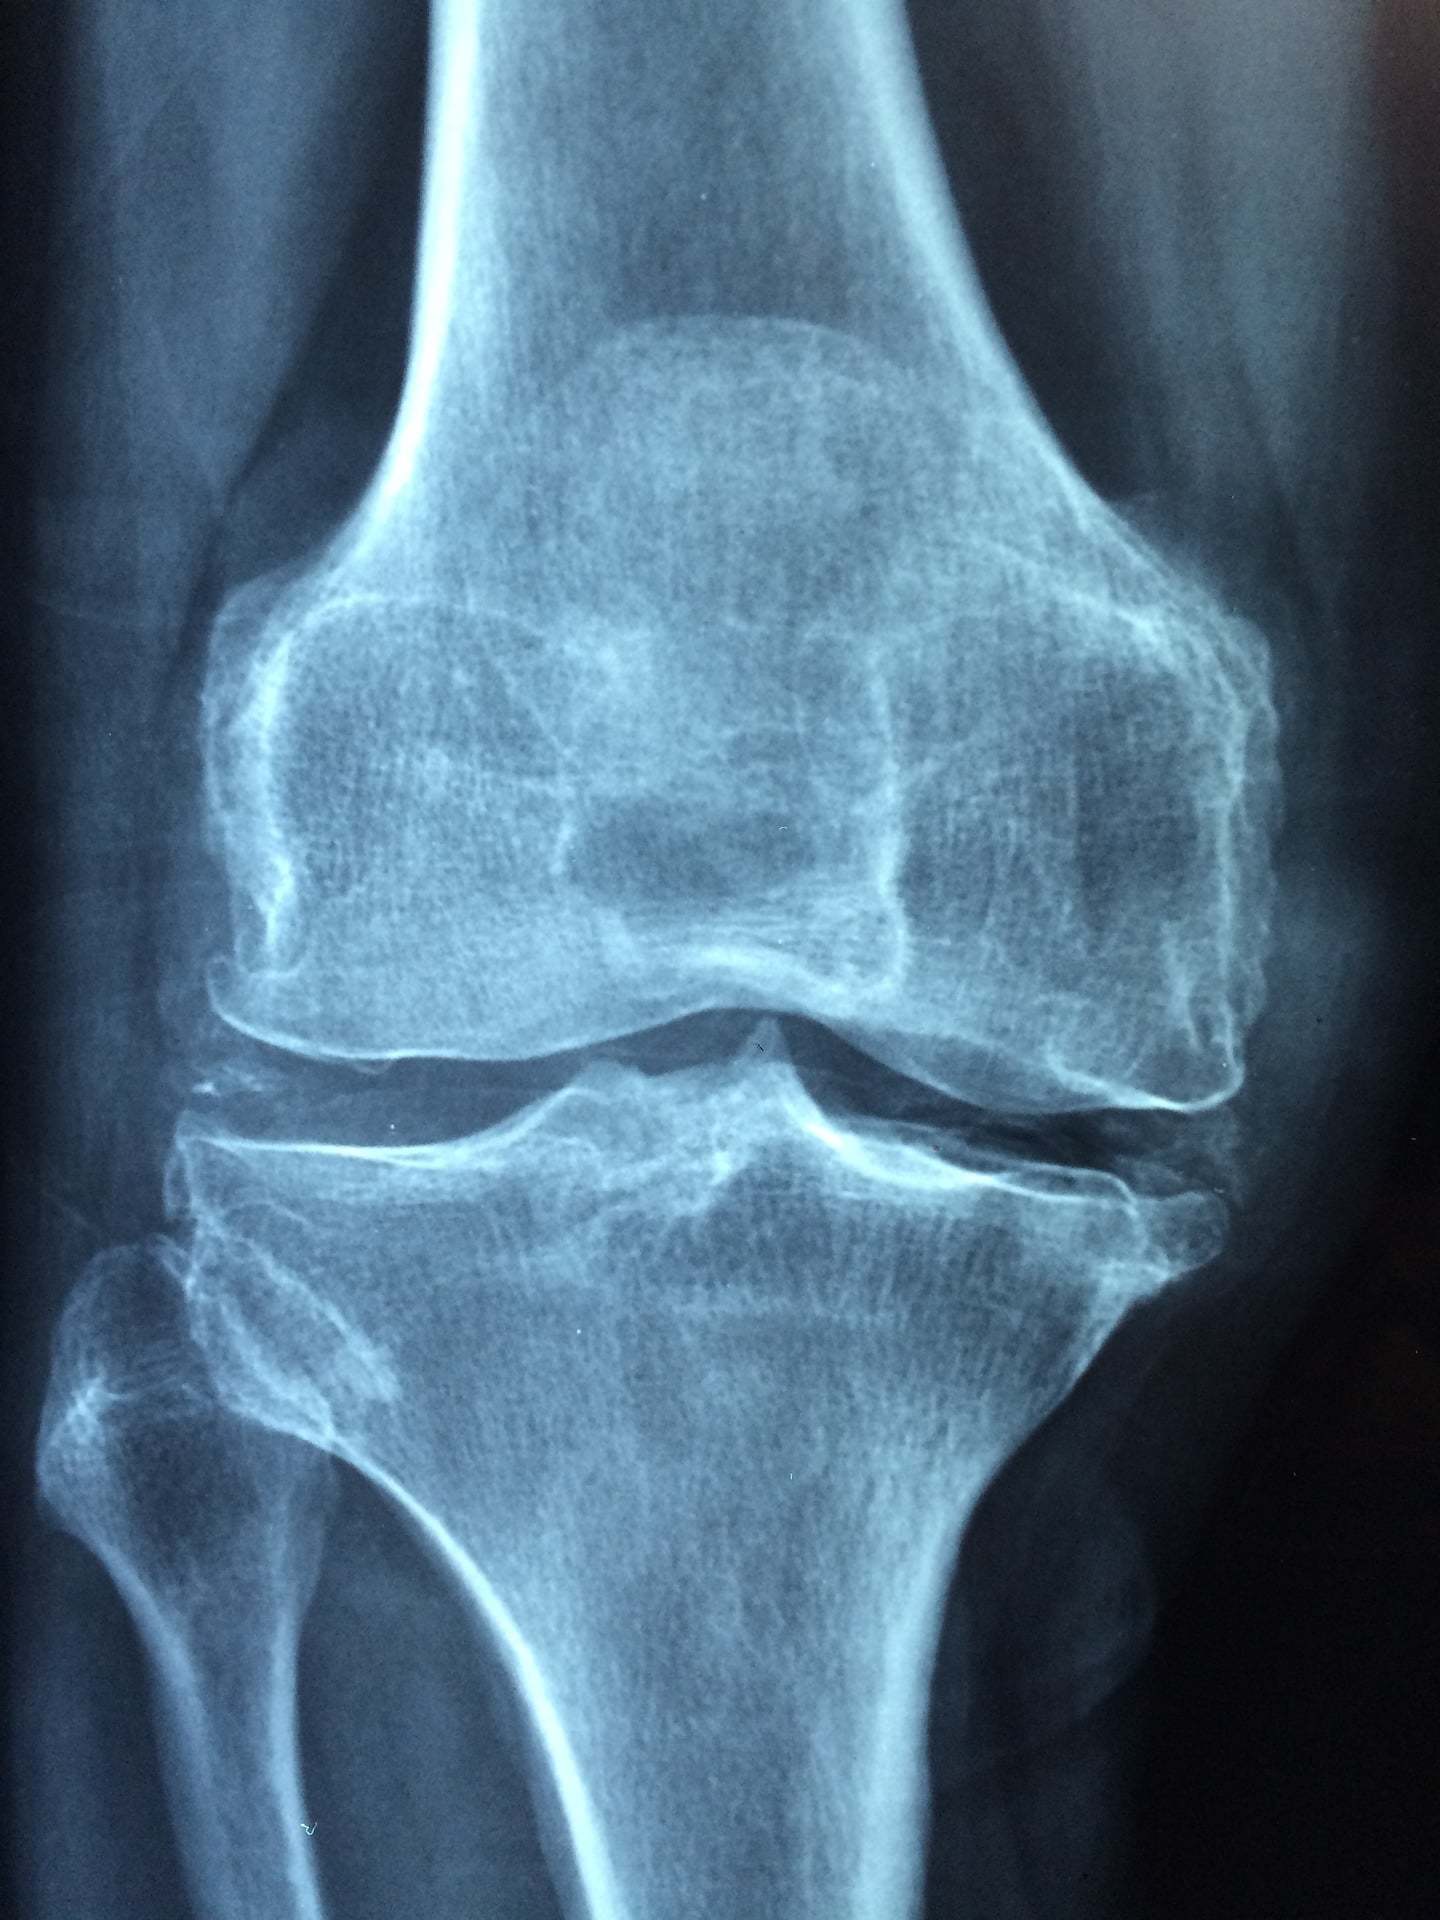

علاج خشونة الركبة تعد هذه المشكلة المرضية لها أسم آخر يطلق عليه تآكل عظام الركبة والذي يصيب المفاصل، فتعتبر تلك المشكلة من أكثر وأشهر المشكلات الموجودة الآن، ففي الولايات المتحدة الأمريكية قد تم عمل مجموعة من الأبحاث والدراسات حول هذا المرض والمصابين به واتضح أن هناك عدد كبير جدا مصاب بهذا المرض، قد وصل عدد هؤلاء الأشخاص إلى ما يقرب من سبعة وعشرين مليون شخص في مختلف الأعمار.

علاج خشونة الركبةهذا التآكل يمكن أن يقوم بإصابة أي نوع من المفاصل الموجودة بجسم الإنسان إلا أن من أبرز الأماكن التي تصاب به في الجسم هي الركبة والحوض والمنطقة الموجودة في نهاية الرقبة ومنطقة أخرى وهى في نهاية الظهر.